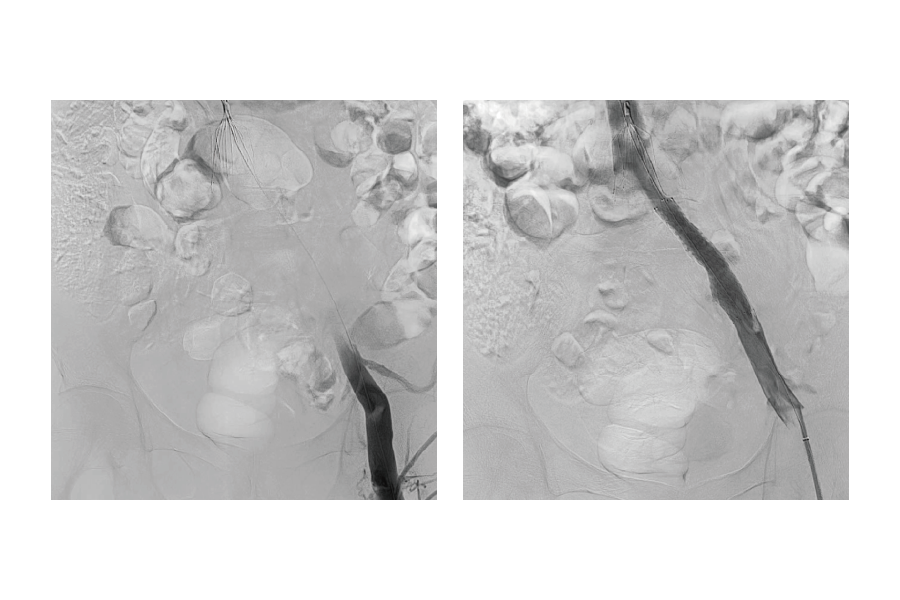

■静脈の血栓

BEFORE

AFTER

別疾患で入院中だった患者様が急性下肢閉塞を起こしましたが、

速やかな治療で改善し、2 日後に退院しました。